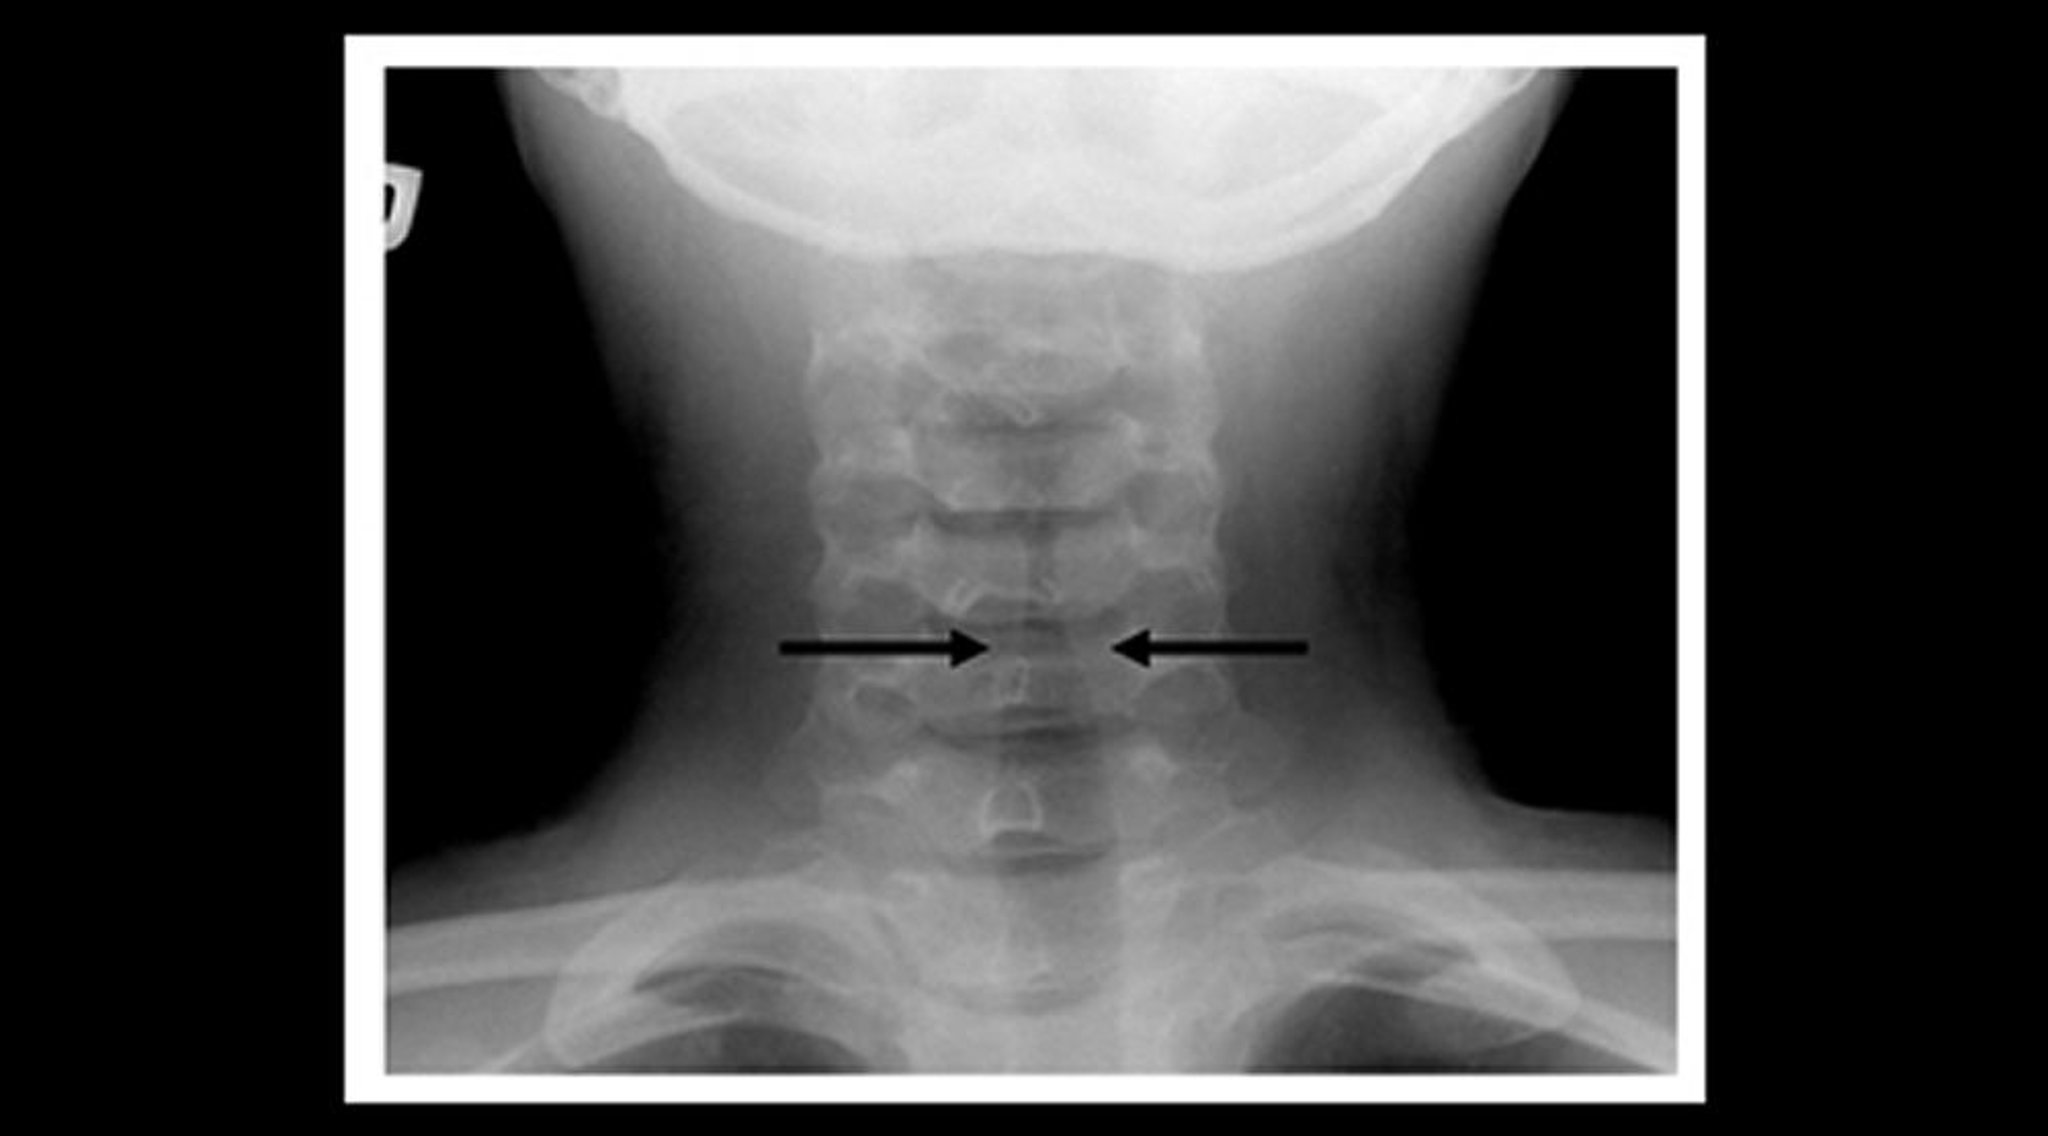

クループの患児の頸部軟部組織X線では,声門下の気道陰影の先細りの狭小化(steeple sign―矢印)および咽頭の気腔の拡大がみられる。